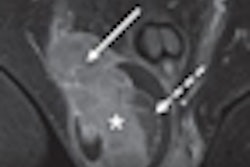

In addition, the U.S. Food and Drug Administration (FDA) recently cleared the first package in what will be several products in IMRIS' MR-guided radiation therapy business. The package is for pelvic, brain, and head and neck imaging, and it includes MRI coil sets and a specialized imaging tabletop intended to help physicians conduct diagnostic MRI scans for radiation therapy treatment planning and simulation, according to the firm.